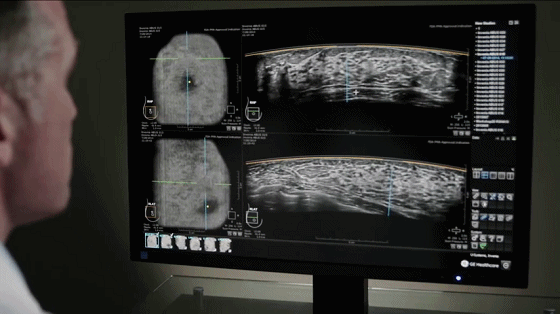

·身为女性,乳房是与生命紧紧相连的一部分,是形体美的重要标志,见证了我们从青涩走向成熟,担负着哺乳的重任。随着人们健康意识的提升和超声检查的普及,越来越多的女性朋友们开始关爱乳房健康,重视乳腺疾病的治疗。 ·乳腺是否有结节、肿块,良性还是恶性,不仅需要我们有更为强烈的自查意识,在日常生活中了解自己家族的遗传史,密切留意身体指标,当发现身体的一些微小信号时及时就医,更重要的是,定期进行乳腺专业检查,让身体恢复到良性循环状态,这是非常有必要的。 为进一步方便患者高效、优质、省时省力的就诊需求,我院特聘专家、阳煤集团总医院「乳腺外科赵春婵主任」将在我院定期坐诊~ 爱德生率先引进 首台ABUS自动乳腺超声系统” 北京协和等国内一线三甲医院 都在用的ABUS ABUS乳腺癌筛查系统,是GE医疗乳腺筛查的最新成果,成为全球目前为止唯一获得FDA PMA认证的乳腺筛查系统,并在全美迅速普及。 2004年初,北京协和与国际乳腺超声学校合作举办了国际乳腺超声研讨会,后引进ABUS乳腺彩超,并于2017年,成立协和-GE ABUS标准化远程读图中心。为国内乳腺超声水平做出了重大的贡献,造福了无数中国女性。 乳腺筛查技术的革新应用 随着我国乳腺疾病发病率日益增加,乳腺癌已是我国女性发病率最高的恶性肿瘤,且越来越趋向于年轻化发展,乳腺筛查成为女性检查中必不可少的项目。 作为目前市面上最先进的自动乳腺超声系统,ABUS乳腺超声系统在保留传统超声临床优势的基础上,更充分实现了其专业化、标准化、精细化,可诊断各种乳腺良性疾病以及乳腺恶性病变,如乳腺增生、乳腺囊性增生病、乳腺炎、乳腺癌等。 ABUS乳腺超声系统可不限次数、重复检查,对于系统时间、年龄无绝对禁忌,经期、孕期可适用,哺乳期、有乳腺疾病等可在医生指导下进行检查。 赵春婵主任乳腺外科门诊 门诊时间 门诊地点 我院门诊楼三层乳腺外科 咨询预约